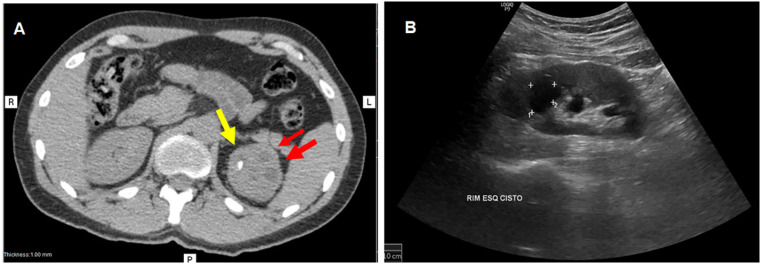

Urogenital tuberculosis (UGT) constitutes a significant extrapulmonary form of tuberculosis, often presenting non-specific symptoms and a prolonged indolent course that leads to delayed diagnosis and treatment, which can result in severe and irreversible complications such as urinary strictures, renal failure, and infertility. This report describes a case of a 38-year-old man with a five-month history of low back pain, hematuria, dysuria, and altered urinary frequency. Initial treatment for a presumed urinary tract infection failed, and subsequent diagnostic investigations showed stones, nodules, and cysts in his left kidney. A positive tuberculin skin test confirmed the diagnosis of UGT and identification of Mycobacterium tuberculosis in urine samples. The patient underwent standard six-month antituberculosis therapy and subsequent retreatment due to persistent symptoms. Despite significant symptom amelioration, irreversible urological sequelae, including infundibular stenosis, polyuria, and nocturia, remained. This case underscores the importance of early suspicion, accurate diagnosis, and timely treatment of UGT to minimize long-term complications. It also highlights the potential need for extended treatment length in complex cases to improve outcomes and reduce sequelae, warranting further research in this area.